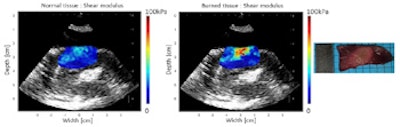

Before and after ablation, the researchers used the probe to record a B-mode ultrasound image and perform SWE mapping. Shear modulus maps recorded before and after HIFU ablation showed clear changes, with thermal lesions clearly seen on all postablation stiffness maps. In contrast, B-mode ultrasound imaging was unable to visualize the thermal lesions.

"SWE provides reliable and precise ablation extension maps," Kwiecinski said. "The link between increased tissue stiffness and thermal coagulation, combined with a high specificity, has been shown. B-mode ultrasound only provides images with very poor specificity and poor contrast."

In an example ablated zone in the chicken breast, the mean shear modulus increased from 4.8 ± 1.1 kPa before ablation to 20.5 ± 10.0 kPa after treatment. In the left atrium, the mean shear modulus increased from 12.2 ± 4.3 to 30.3 ± 10.3 after ablation. In one of the left ventricle ablations, the researchers inserted an ex vivo esophagus around the transducers and performed HIFU and imaging through the esophagus. Here, the mean stiffness increased from 21.2 ± 3.3 to 73.8 ± 13.9 kPa in the central region.

Shear modulus maps of the left ventricle, before (left) and after (center) ablation, with SWE and HIFU performed through an esophagus. The mean shear modulus increased from 21.2 ± 3.3 kPa to 73.8 ± 13.9 kPa in the central-8-mm-diameter zone. A photograph of the gross pathology section is shown on the right.

As initial tissue stiffness varied significantly between samples, the researchers calculated the ratio of shear modulus before and after ablation, setting a ratio of 1.7 (based on previous work) as a threshold to discriminate ablated and normal tissue. The mean ratios calculated for three chicken breast ablations, two ventricular ablations (one through the esophagus), and two atrial ablations were approximately 3.8, 3.0, and 2.2, respectively.